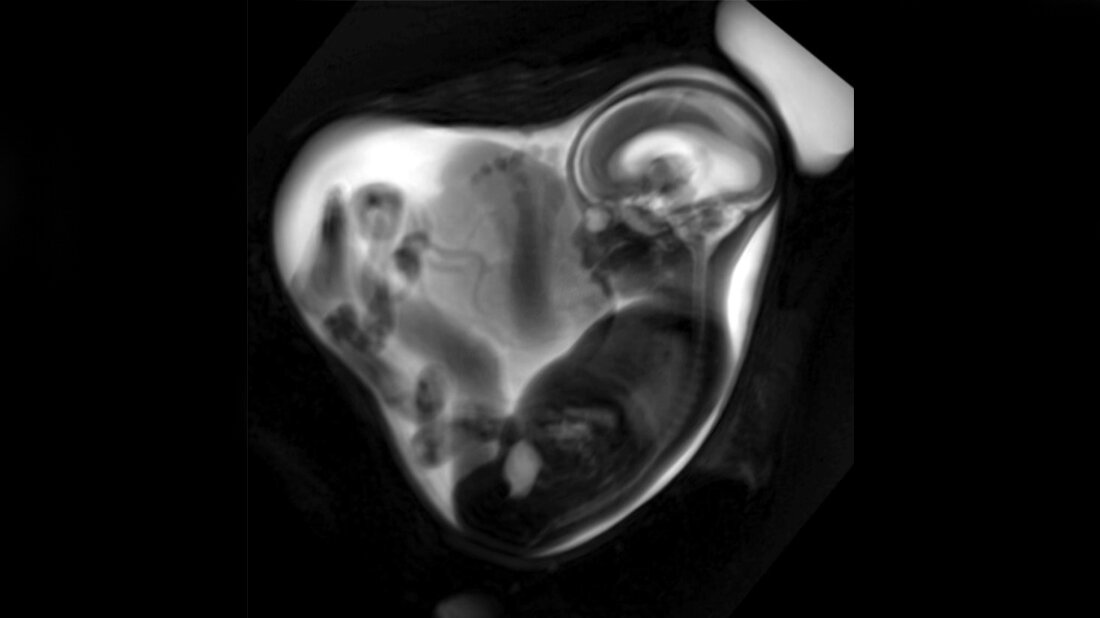

Die fetale MRT ist eine spezialisierte Bildgebungsmethode der pränatalen Diagnostik, die etwa ab der 18. Schwangerschaftswoche eingesetzt werden kann. LMU Klinikum München

Mittels pränataler Magnetresonanztomografie (MRT) haben Forscher ein teilweise deutlich reduziertes Lungenvolumen bei Feten nachgewiesen, deren Mütter in der Schwangerschaft eine unkomplizierte SARS-CoV-2-Infektion durchgemacht haben.

Diese Reduktion des Lungenvolumens war laut Studie besonders deutlich, wenn die Infektion im letzten Drittel der Schwangerschaft stattgefunden hatte. Die Daten wurden erhoben, bevor eine Impfung gegen SARS-CoV-2 verfügbar war. Die Forscherinnen und Forscher um Prof. Dr. Sophia Stöcklein von der Klinik und Poliklinik für Radiologie des LMU Klinikums und Privat-Dozentin Dr. Anne Hilgendorff vom Zentrum für Comprehensive Developmental Care des LMU Klinikums und von Helmholtz Munich haben insgesamt 34 Schwangere respektive Feten mittels fetaler MRT untersucht. Die fetale MRT ist eine hochspezialisierte Untersuchungsmethode, die es ermöglicht, die Entwicklung fetaler Strukturen bereits vor Geburt detailliert zu untersuchen. Die Frauen hatten sich zu unterschiedlichen Zeitpunkten mit der Alpha-Variante des Coronavirus infiziert, bestätigt durch PCR-Test. Die Lungen der Feten wurden mittels Magnetresonanztomografie vermessen, das Lungenvolumen bestimmt und mit Feten aus einer sogenannten Referenzkohorte verglichen, bei denen keine Infektion während der Schwangerschaft stattgefunden hatte.